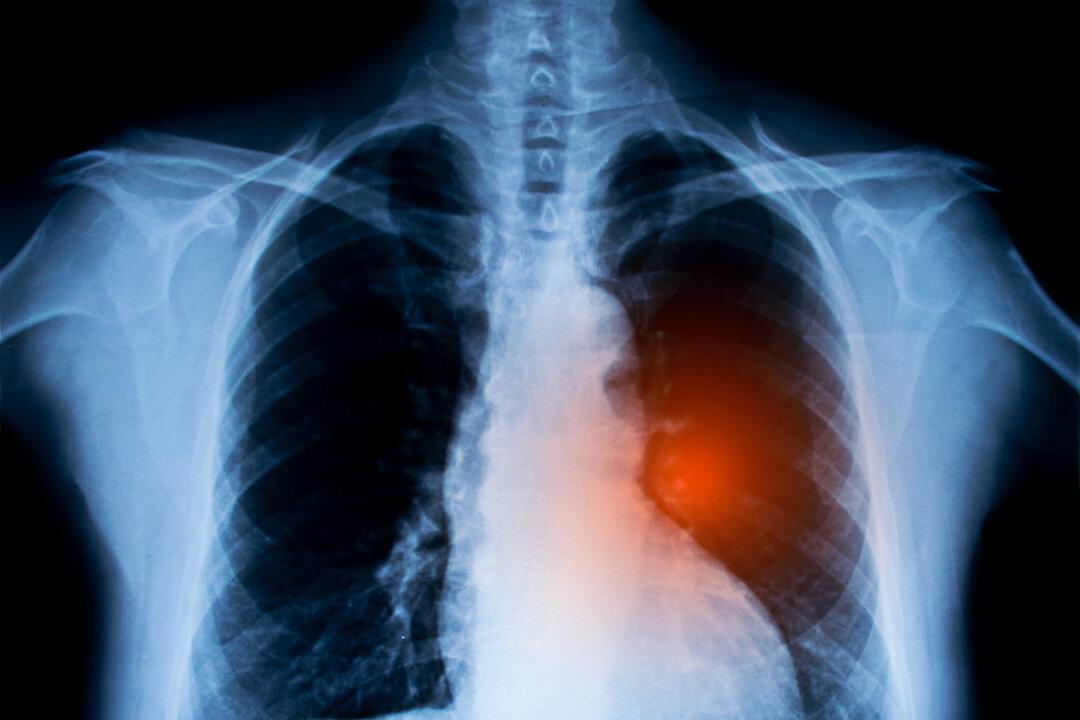

A nearly decade-long study revealed that a once-a-day pill can reduce the risk of death from lung cancer by more than half, offering hope for improved patient outcomes and potentially saving millions of lives.

Recently published in the New England Journal of Medicine (NEJM), the research involved 682 patients, including those diagnosed with non-small cell lung cancer (NSCLC), which accounts for 80 to 85 percent of all diagnosed lung cancers.